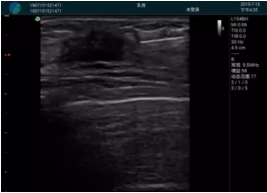

甲狀腺囊性結(jié)節(jié),囊壁鈣化,透聲好

甲狀腺囊性占位